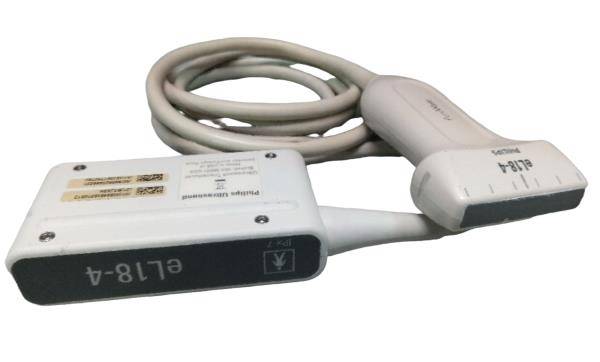

Probe Function: 3.5MHZ convex, abdominal organs

The ultrasound scanner is a crucial tool in modern healthcare, particularly for monitoring pregnancy. Equipped with both convex and transvaginal probes, it provides exceptional 3D imaging capabilities. This means doctors can obtain clearer, more detailed images of the fetus, helping in making informed decisions regarding prenatal care. Because the images are so precise, healthcare providers can detect potential abnormalities early, enhancing the safety of both mother and child.